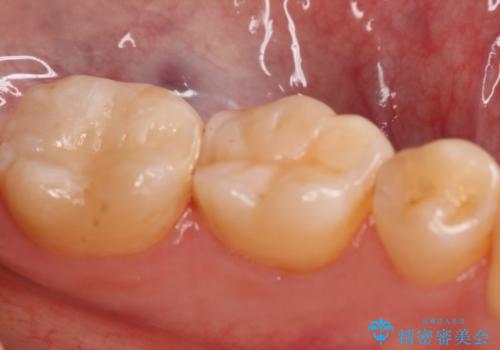

- 左下7番のCR劣化を自費治療にて希望された患者様です。

切削量を考慮してセラミックインレーでの治療を選択しました。

CR直下と隣接面にう蝕が進行していたので、除去した上で形成、印象しています。